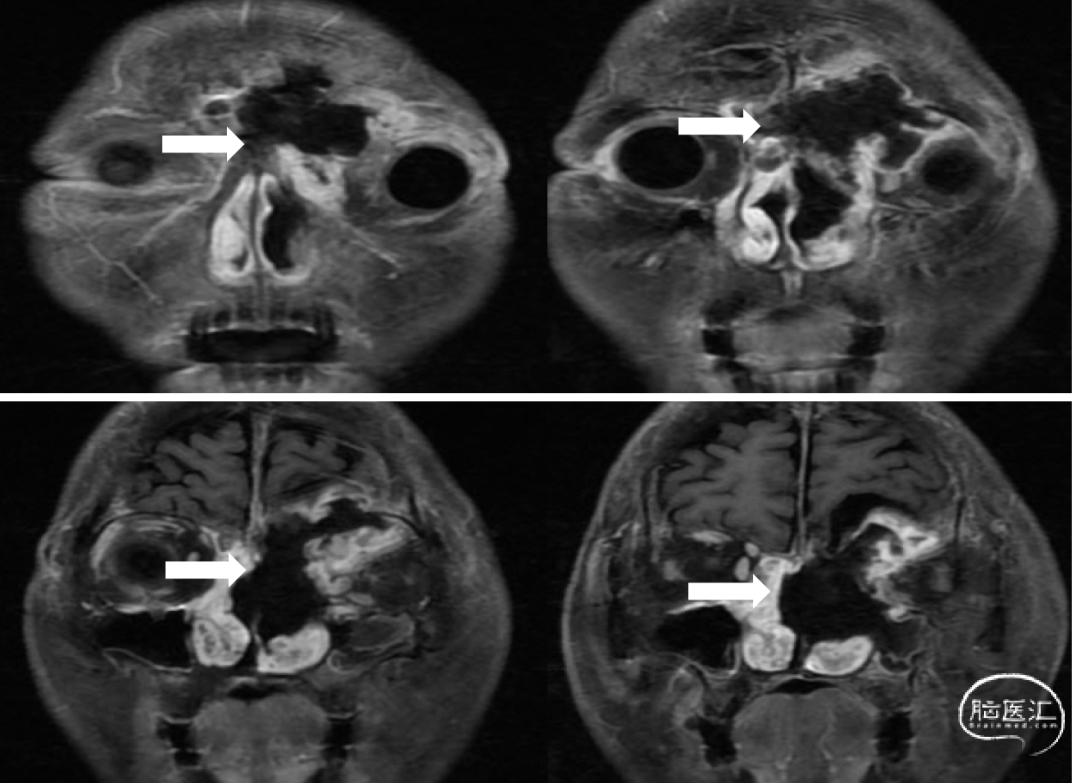

术后MRI检查结果:显示颅内、额窦、筛窦、眼眶、鼻腔、蝶窦及上颌窦内肿瘤均已切除,MRI显示高信号为脂肪组织。